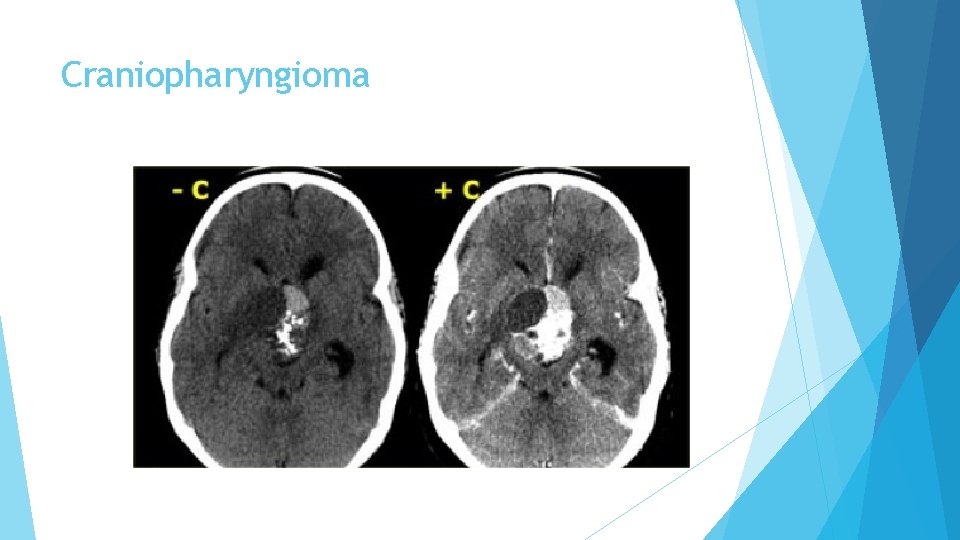

Craniopharyngioma is the third of the three pathologies derived from Rathke's cleft epithelium. Technically these are benign tumors, but unlike Rathke's cleft cysts, they have thick walls and are locally invasive. Macroscopically, it is a complex mass with multiple nodules at the base of the brain, sinuating along the fissures. Often, it can not be completely resected.

Craniopharyngioma In over 50% of cases craniopharyngiomas have a pathognomonic appearance. A compressed pituitary gland can be identified. There is a large intrasellar and suprasellar mass with cystic and enhancing components as well as calcifications. These findings in a child are virtually pathognomonic for craniopharyngioma (perhaps with only a dermoid in the differential diagnosis).

Craniopharyngioma